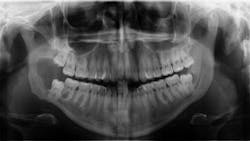

A healthy, 22-year-old female presents for a comprehensive examination. She has no chief complaints and no caries. The patient is referred to an oral surgeon for removal of wisdom teeth. Following that, all contact is lost (figure 1).